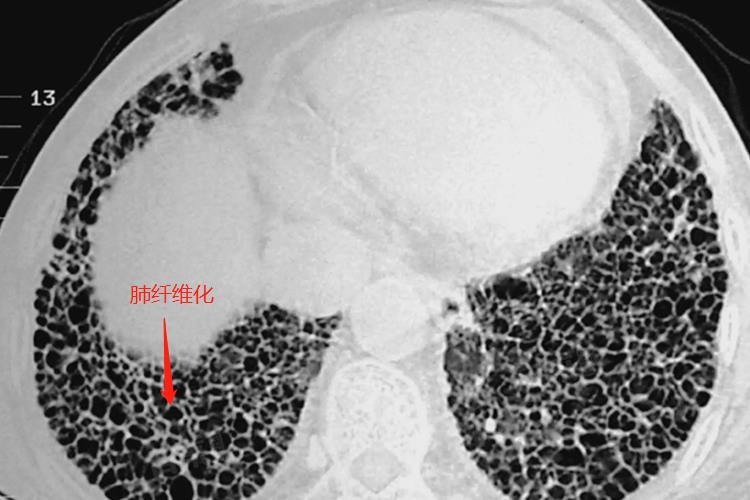

- 右肺中叶纤维灶是肺部损伤或感染后,在修复过程中纤维组织增生并遗留的痕迹,纤维灶在影像学上常表现为索条状高密度影。纤维灶的形成主要是由于肺部受到炎症、感染、损伤等刺激后,纤维母细胞增生并分泌胶原蛋白进行修复,过度增生则可能形成纤维灶,常见的病因包括肺结核、肺炎、肺癌等。

- 如果纤维灶是由于肺部炎症或感染治愈后遗留的,且面积较小,对肺功能影响有限,患者通常无明显临床症状,此时无需特殊处理,定期复查即可。如果纤维灶面积较大或位于关键部位,可能影响肺功能,导致患者出现咳嗽、咳痰、胸闷、气急等症状。

- 此时需要进一步检查和治疗,特别是当纤维灶由特发性肺间质纤维化引起时,可能导致肺部大面积纤维化病变,严重影响患者的生活质量,属于比较严重的情况。如果纤维灶是由于肺癌等恶性肿瘤引起,严重程度则取决于肿瘤的分期和治疗方法。